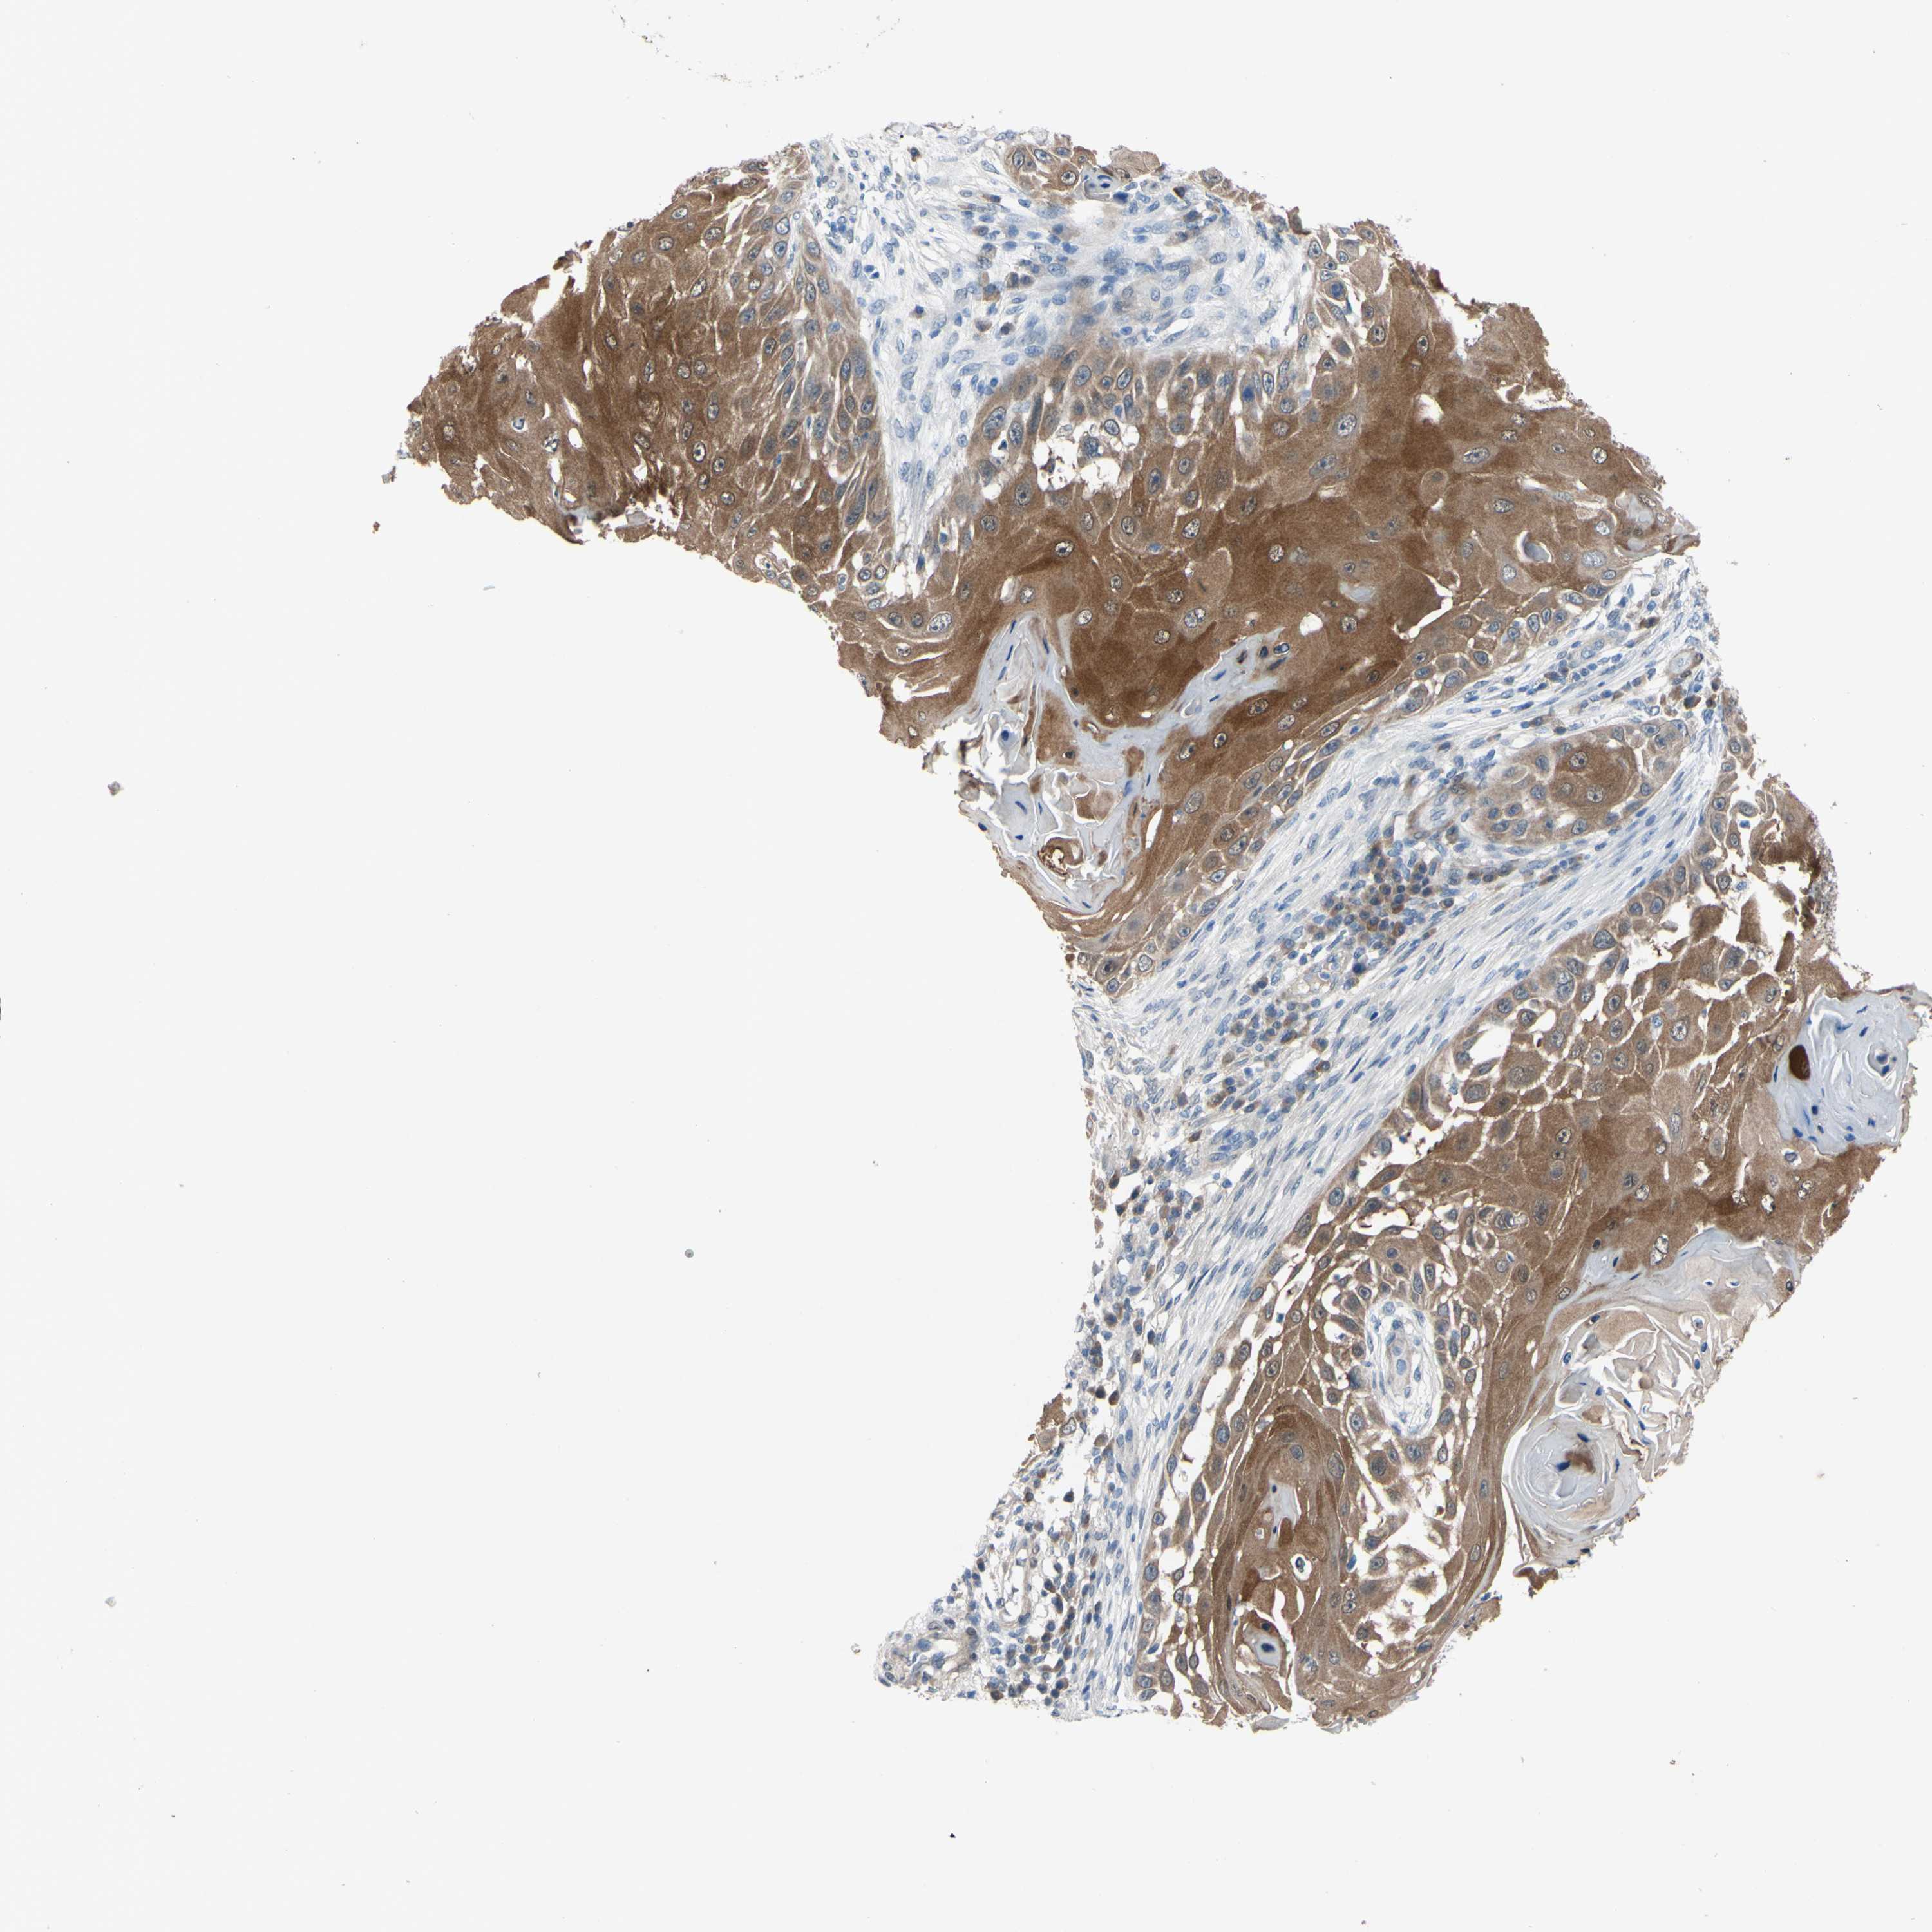

Basal cell and squamous cell cancer

SKIN CANCER - Protein expressioni

A mouse-over function shows sample information and annotation data. Click on an image to view it in a full screen mode. Samples can be filtered based on level of antibody staining by selecting one or several of the following categories: high, medium, low and not detected. The assay and annotation is described here.

Each image is clickable and will lead to virtual microscopy that enables deeper exploration of all samples and also displays staining intensity scores, fraction scores and subcellular localization as well as patient and tissue information for each sample.

Antibody CAB009208

Staining

High

Medium

Low

Not detected

Intensity

Strong

Moderate

Weak

Negative

Quantity

>75%

75%-25%

<25%

None

Location

Nuclear

Cytoplasmic/membranous

Cytoplasmic/membranous,nuclear

Squamous cell carcinoma, NOS

Basal cell carcinoma